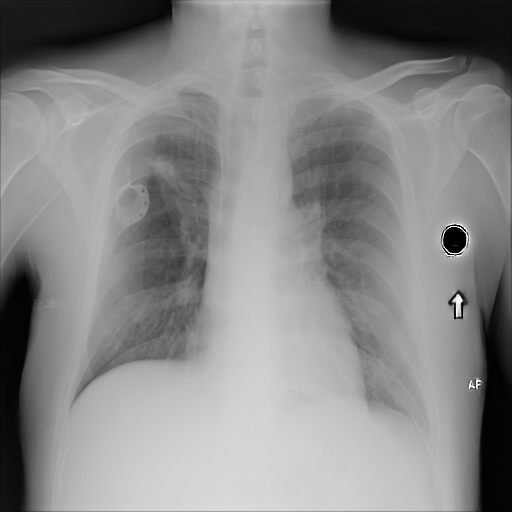

7.2 Qualitative assessment of LDP-processed CXR images

Here, we assume two possible privacy leakage scenarios. To CXR images, we intentionally add features that can lead to the re-identification of the subject appearing in a CXR image. The first feature is an artificial block marker. The second feature is a rare anatomical abnormality known as situs inversus simulated by flipping a CXR image along the vertical axis. Figs. 3(a) and 3(c) show CXR images with the artificial block marker. Fig. 5(a) shows a flipped CXR image to represent a case of situs inversus. We applied DP-GLOW to these CXR images. In Figs. 3(b) and 3(d), the image domain LDP fails to obfuscate the artificial block marker with a moderate privacy budget. In contrast, in Figs. 4(b) and 4(d), DP-GLOW successfully obfuscated the artificial block marker with the moderate privacy budget. On the other hand, the anatomical shape of the chest and the abnormal opacity (hilar regions in the case 1) are preserved. In Fig. 5(b), we observed that the right edge of the heart does not become obfuscated with the image domain LDP. In contrast, in Fig. 6(b), we observed that the right edge of the heart becomes obfuscated and the heart appears at the center of the thoracic cage with DP-GLOW. However, DP-GLOW with this privacy budget is insufficient to almost completely erase the feature of situs inversus.